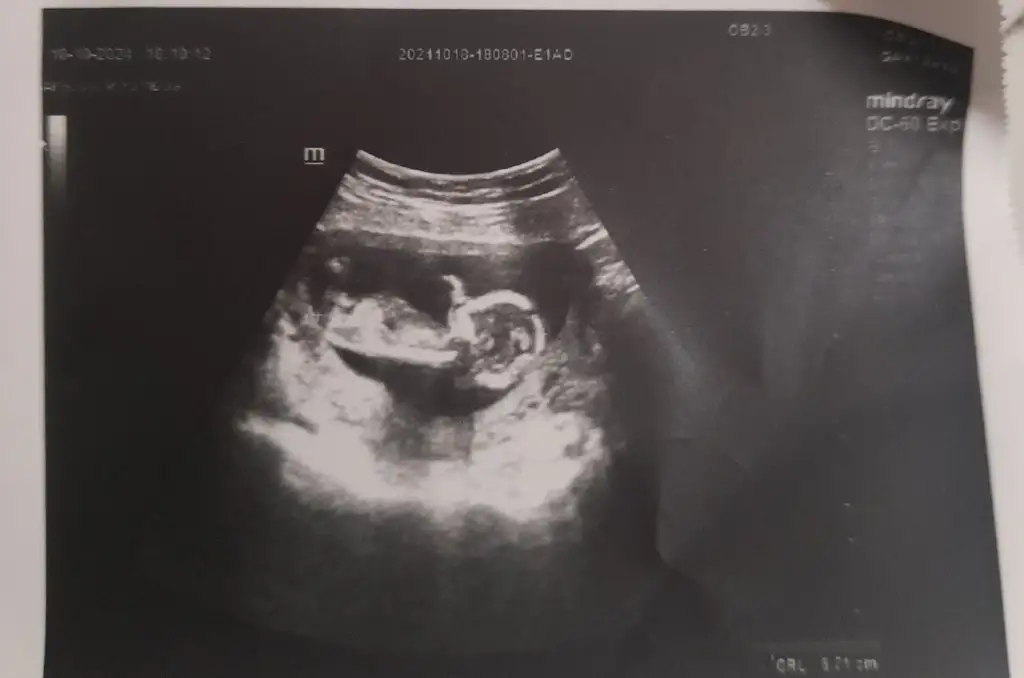

Kızzkızlarrr son kez cinsiyet tahmini yapabilir misinizzz

doktor yüzde 80-90 bir tahminim var dedi ama tam cinsiyeti göremedisizceee teyzeleriii

Bebek gelişirken cinsel organında bir açı oluşur orada da bir açı var açı dikeyse erkek yatay ise kızdır oradaki açı biraz yatay sizin nub teorisi. Benim kızımda da tutmuştu bu teorineye göre tahmin ettiniz acaba içimde bir umut oluştu